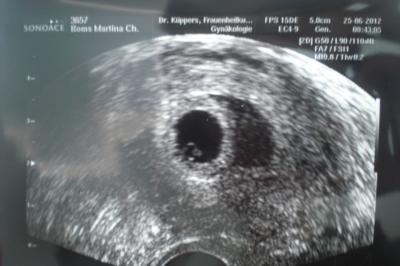

So nun kann ich berichten. Bin grade erst nach Hause gekommen und die Jungs schlafen nun. Zuerst wurde mir Blut abgenommen und Blutdruck gemessen. Dann gab es Ultraschall. Der Arzt sagte das der ET der 08.02.2013 sei. Danach meinte er ich sei in der 7. SSW. Der Internet Rechner sagt aber 8. SSW. Das verwirrt mich etwas. Am 05.07 hab ich wieder Termin

Bild zu Update SS - Forum für Februar - Mamis